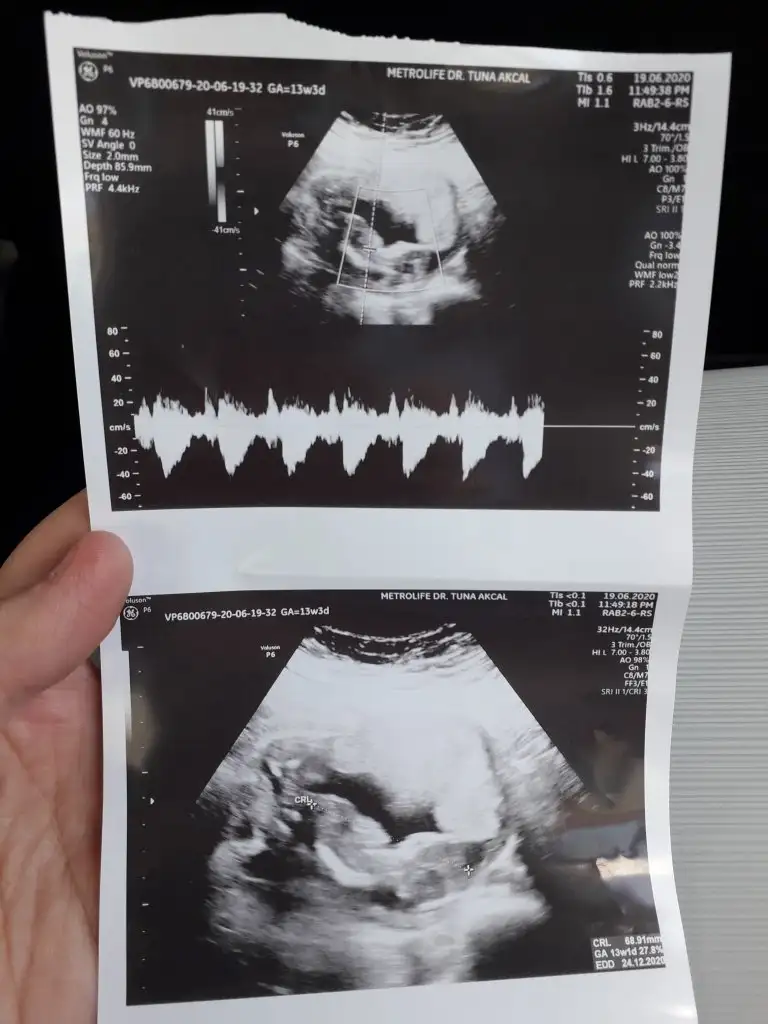

Kız sanki emin olmadım çok net değil usg varsa 11 yada 13 hafta usg olursa paylaşınSelam canlar, anlayan varsa bize de bakabilir mi acaba

Doktorda kız dedi zaten 11+5 de gıttım buna daha yeni canım :) obur ay gıderım bide. Teşekkür ederim tatlımKız sanki emin olmadım çok net değil usg varsa 11 yada 13 hafta usg olursa paylaşın

Nub olmaz bu haftalarda hayırlısıikra meyra canim kesemize erkek gibi demistin ,13 haftalik olana dr erkek dedi sen kiz gibi demistin tam net cikmamis ama dün kontrolum vardi 18haftaligiz dr kız gibide diyebilirim dedi yine netlesmedi cinsiyetimiz son usg den belli olmuyor dimi ?